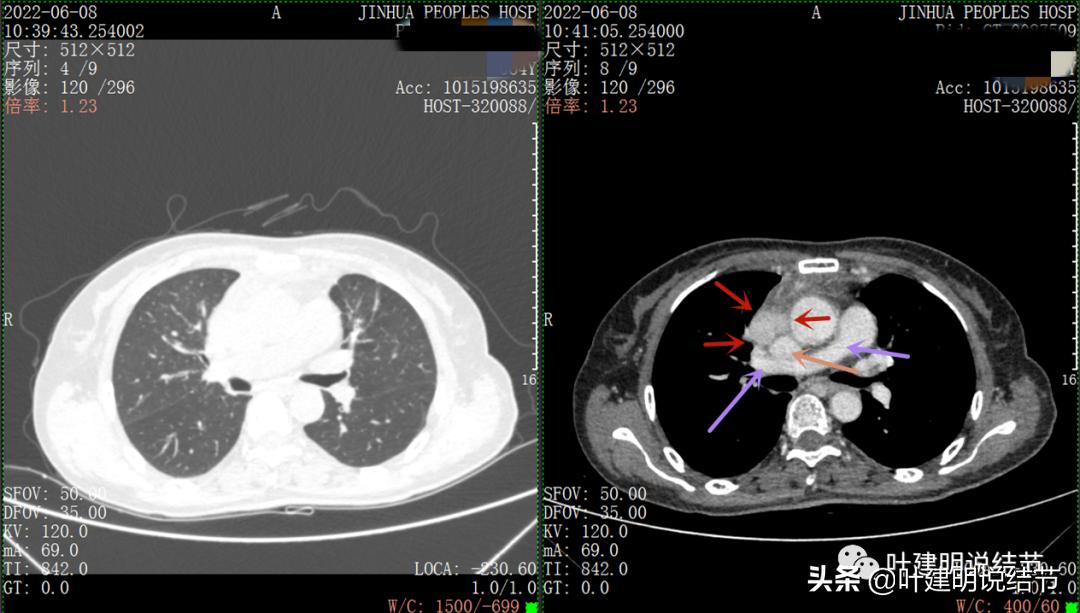

以下图片左侧是肺窗,右侧是纵隔窗。红色箭头示病灶,桔色箭头示无名静脉,黄色箭头示支气管,砖色箭头示上腔静脉,蓝色箭头示主动脉,紫色箭头示肺动脉。

绿色箭头示近膈面处,心脏边病灶

此灶与主病灶不是完全相连的

病灶占据前纵隔从上到下全程,多中心,密度不均,对心脏与大血管有压迫,没有明显侵犯

病灶表面不平,中间有坏死